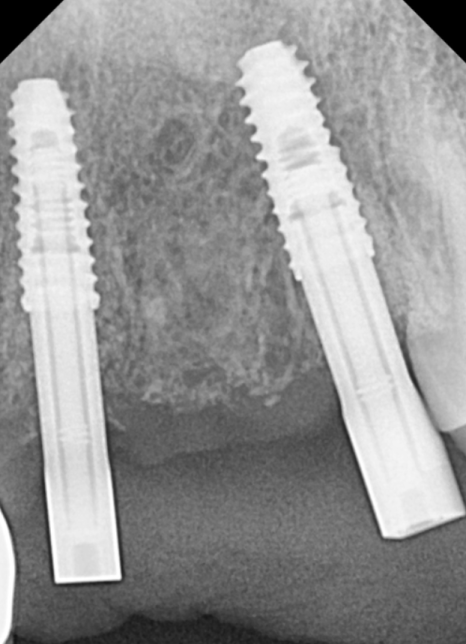

정확한 위치에 임플란트 식립을 끝낸 뒤

임시 치아까지 끼워드리기 때문에,

치아 빈자리 걱정 없이

바로 일상생활이 가능하답니다.^^